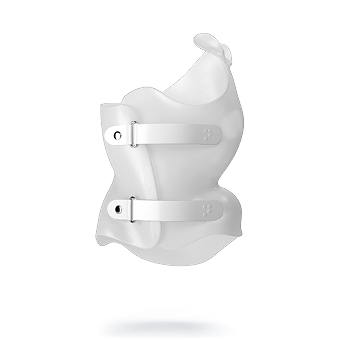

الحزام الفعّال هو الذي:

يحافظ على التقوس الطبيعي للظهر

يتكيف مع شكل القفص الصدري

لا يسبب ضغطًا مفرطًا يعيق الالتزام

لذلك، الأحزمة المصممة خصيصًا بناءً على التحليل ثلاثي الأبعاد تحقق نتائج أفضل من الأحزمة التقليدية العامة.

الحزام المصمم بشكل فردي مثل PioBrace يعطي نتائج أفضل

امنح طفلك فرصة أفضل لمستقبل صحي مع حزام PioBrace المتطور من مركز الرواد. يتميز هذا الحزام بتقنيات تقويم متقدمة تضمن نسبة تصحيح عالية لاعوجاج العمود الفقري، مع اعتماد فريق طبي متخصص يراقب التقدم بشكل مستمر لضمان عدم تفاقم الانحناء مستقبلاً. اختروا مركز الرواد، حيث تلتقي الخبرة الطبية بأحدث الابتكارات، لنوفر لطفلكم علاجًا مخصصًا وآمنًا يعيد التوازن لجسمه بثقة واحترافية. صحتهم أمانة ونحن هنا لنحافظ عليها.

لماذا يجب عليكم اختيار حزام PioBrace؟

- راحة استثنائية: يتميز حزام PioBrace بتصميمه الذي يوفر أقصى درجات الراحة للأطفال طوال فترة العلاج.

- فعالية مثبتة علميًا: يساعد الحزام في إيقاف تقدم الاعوجاج وتقليل الحاجة إلى التدخل الجراحي.

- سهولة الاستخدام: يمكن ارتداؤه لفترات طويلة دون التسبب في أي إزعاج للأطفال.

- موثوقية وجودة عالية: يُصنع بأحدث التقنيات لضمان أقصى درجات الراحة والكفاءة.